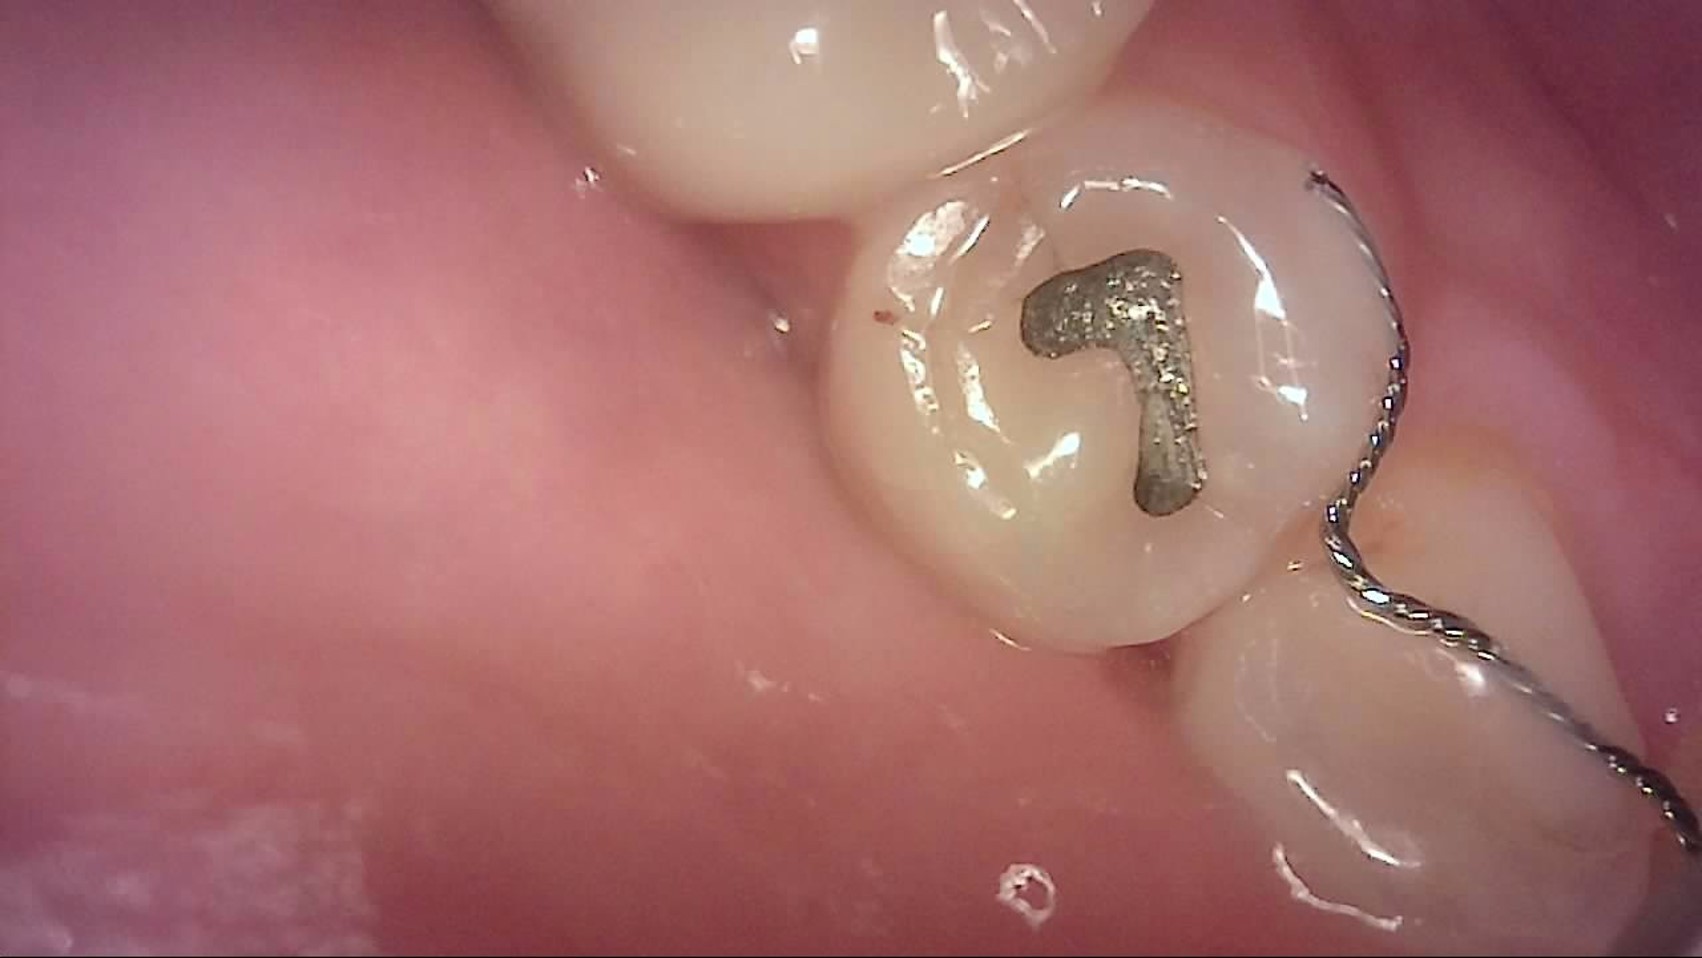

Crack

큐레이캠프로, 큐레이펜씨